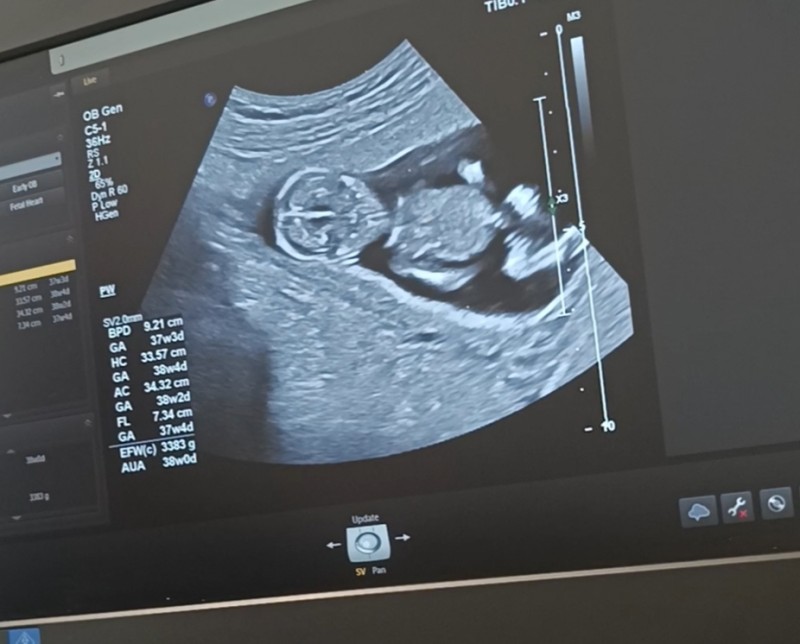

imagebanada yorum yaparmısınız

Kız sizinki

Nub çok yatay çıkmış diklik yok o yüzden kız dedım

Kiz diye sallamak istiyorum hayırlısı olsun